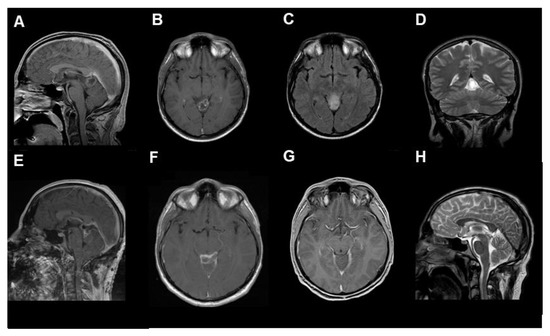

- Case 1:

- Case 2:

- Case 3:

- Case 4:

- Case 5: